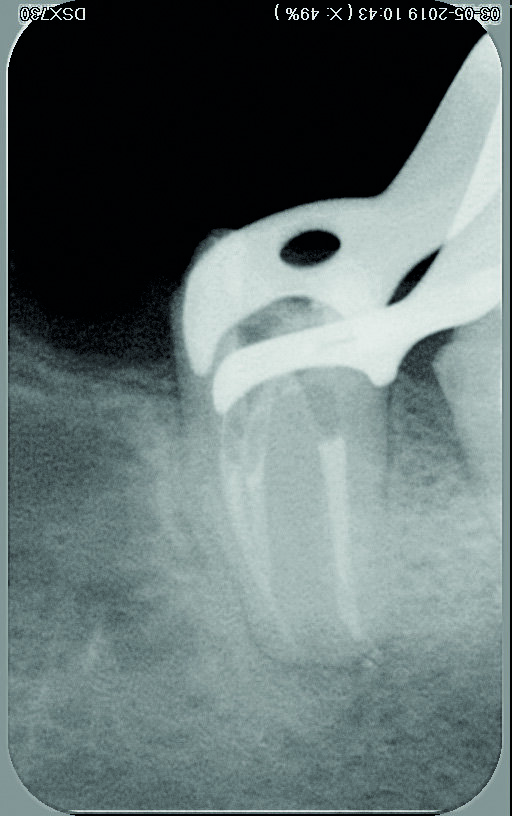

Une femme de 44 ans, sans antécédents médicaux particuliers, nous est adressée pour le retraitement endodontique de sa première molaire inférieure gauche qui cause une douleur depuis une semaine. La dent est très sensible à la percussion, ne présente aucune mobilité, et le résultat du sondage parodontal se situe dans les limites physiologiques. Une première radiographie est prise (Fig. 1). Elle montre trois fragments d’instruments fracturés demeurés dans deux canaux (mésial et distal) après le traitement endodontique précédent, ainsi que des signes d’une pathologie péri-apicale. Les résultats des examens cliniques et radiographiques conduisent à un diagnostic de parodontite apicale symptomatique de la dent déjà traitée et suggèrent la nécessité d’un retraitement.

Fig. 1 : Radiographie initiale.